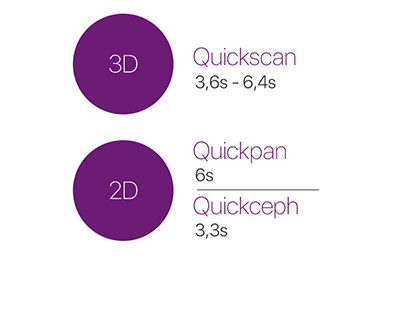

La technologie DCIII applique le capteur à conversion directe innovant qui a révolutionné l’imagerie 2D aux filtres PiE (Powerful image Enhancer). Les systèmes standards prévoient une conversion des rayons X en lumière visible, qui est traduite à son tour en signaux électriques pour donner naissance à l’image numérique. À l’inverse, avec la technologie DCIII, le capteur reçoit et génère directement les rayons X, ce qui augmente la sensibilité et l’efficacité sans perte de détails. Cela permet d’obtenir des images haute résolution avec un niveau de contraste supérieur et à faible dose, mais également extrêmement détaillées, y compris des protocoles de balayage rapide à très faible dose tels que QuickCEPH ou QuickPAN.

BALAYAGE RAPIDE À TRÈS FAIBLE DOSE

Les protocoles avancés QuickScan, disponibles tant pour les examens 2D que pour les acquisitions 3D, permettent d’obtenir des images précises avec des doses faibles par rapport à une acquisition standard. Ils représentent l’outil idéal pour les contrôles post-opératoires et l’identification d’éventuelles macrostructures (comme par exemple des dents incluses ou des agénésies).

| Temps de balayage minimum | 6,4 s | 3,6 s |